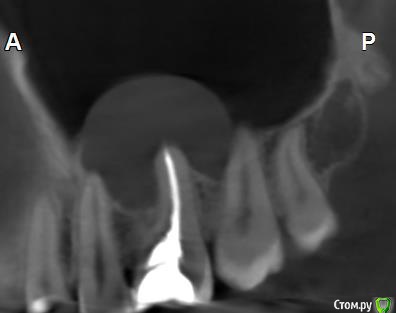

Здравствуйте! Верхний правый шестой зуб пломбировали 3 месяца назад. Примерно месяц назад он начал ныть, после насморка, сначала периодами, а теперь почти постоянно. При постукивание (ощущается не совсем так, как другие зубы) и пальпации десны он не болит. 2,5 месяца назад удаляли кисту из гайморовой пазухи. Может ли быть это какое-то воспаление и есть ли вероятность устранить его какими-нибудь антибиотиками, если да, то как, или может удалить зуб? Если есть воспаление, то какие могут быть последствия если не удалить зуб?

(Снимки с КТ, первые 8(Image) - сделаны сейчас,по 4 в разных проекциях, вторые 8(Before) - сделаны 5 месяцев назад до удаление кисты и повторного пломбирование зуба( до повторного пломбирование он реагировал на горячее, был запломбирован 3 года))